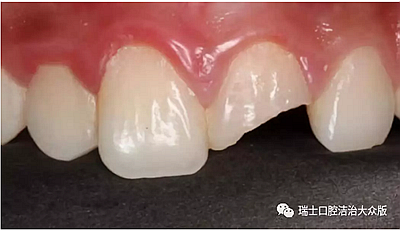

1、冠折(圖4)

成人牙齒外傷了怎么應急處理?

圖4. 冠折

如果折斷的范圍局限于牙釉質(zhì)可能沒有明顯的癥狀,但如果折斷至牙本質(zhì)甚至牙髓,就會出現(xiàn)牙齒的敏感和疼痛。此時不論折斷范圍如何,均可將折斷的部分找回,帶至醫(yī)生處就診,同時避免冷熱刺激和進食刺激性食物。